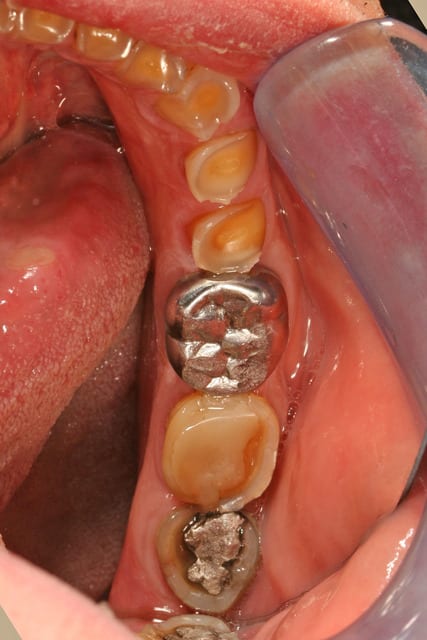

les modèles d'étude

on voit bien l'abrasion liée au bruxisme

l'érosion liée à l'acidité (une bière tous les soirs avant le repas, une pomme tous les soirs en dehors du repas)

l'usure des prémos liée a de mauvaises habitudes dans son métier (tournevis ou stylo au coin de la bouche)